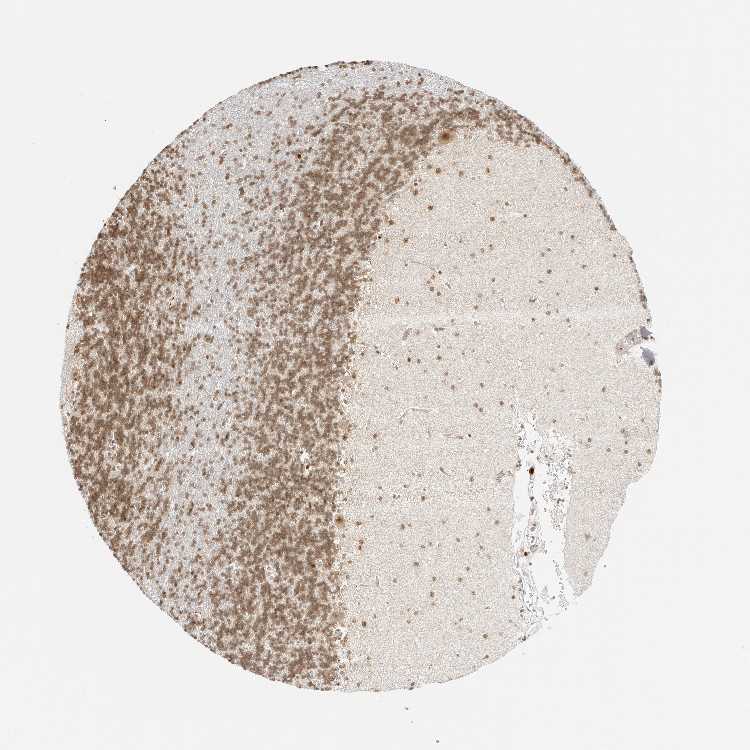

CEREBELLUM - Antibody stainingi

Antibody staining in the annotated cell types in the current human tissue is reported as not detected, low, medium, or high, based on conventional immunohistochemistry profiling in selected tissues. This score is based on the combination of the staining intensity and fraction of stained cells.

Each image is clickable and will lead to virtual microscopy that enables deeper exploration of all samples and also displays staining intensity scores, fraction scores and subcellular localization as well as patient and tissue information for each sample.

Antibody HPA027573Antibody HPA027574Antibody CAB015413

Purkinje cells LowMediumLow

Cells in granular layer LowMediumNot detected

Cells in molecular layer Not detectedMediumNot detected